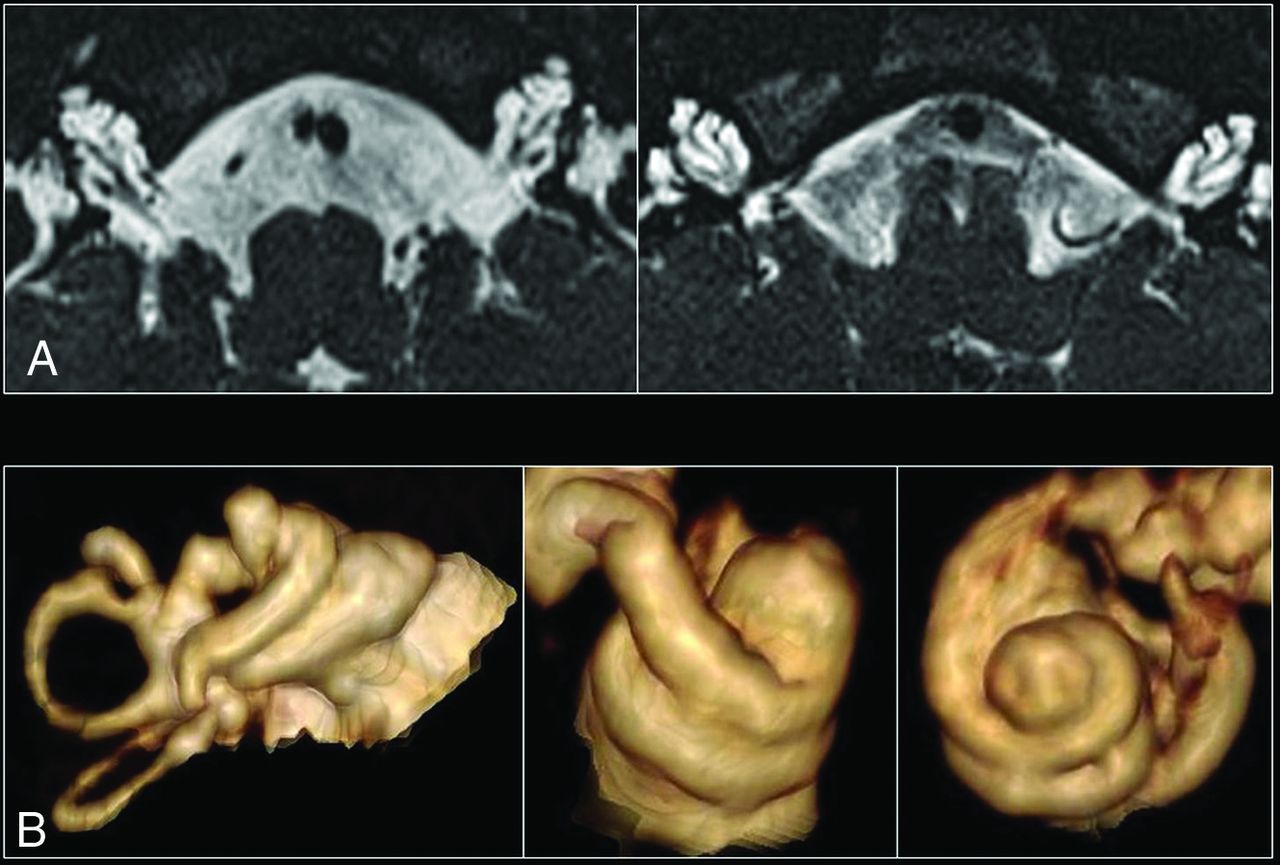

This retrospective study included patients with sensorineural hearing loss who underwent MR imaging at a tertiary pediatric hospital (Children’s Hospital at Westmead, Sydney) between 2006 and 2019 and demonstrated a pathognomonic DFNX2 inner ear abnormality (Fig 1). A second comparison group of age-matched patients with or without hearing loss and normal MR imaging brain findings was extracted from the same hospital. None of the controls had hypothalamic dysfunction.

A, High-resolution axial T2 images of both inner ears in a patient with incomplete partition type III. The 3 main features include a dilated internal auditory canal, incomplete separation of the basal turn of the cochlea from the internal auditory canal, with an absent lamina cribrosa and modiolus. B, 3D reconstructions of several cochleae with incomplete partition type III, which demonstrate the presence of interscalar septa and cochlear turns.

There were 11 patients with image-diagnosed DFNX2 between 2006 and 2019 in our population. One patient was excluded due to the lack of MR images available. The remaining 10 patients with DFNX2 were all males and had the pathognomonic temporal bone deformity (Fig 1) with absence of the lamina cribrosa between the basal turn of the cochlea and the internal auditory meatus (IAM) (κ = 1). Eight patients with DFNX2 had a dysplastic vestibule (κ = 0.86), and 6 showed a dilated endolymphatic duct (κ = 0.61). The mean age at the time of performing the first MR imaging was 78.6 months, with a median value of 22 months (range, 6–270 months).